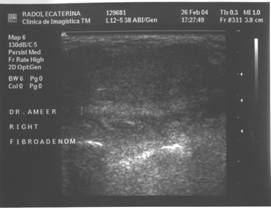

Fibroadenomul este tumora benigna cel mai frecvent asociata cu calcificari. Definitia lor histologica, corespunde unei proliferari fibro-epiteliale benigne. Exista tipuri pericanaliculare, intracanaliculare si forme mixte.